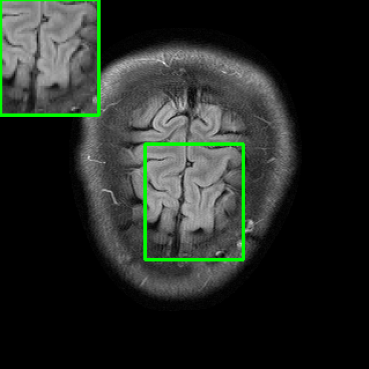

Results for the FastMRI Brain Dataset: we present the robustness results of the proposed approaches w.r.t. additive noise. In particular, the evaluation is conducted on the clean, noisy (with added Gaussian noise), and worst-case perturbed (using PGD for each method) measurements. Fig. 3 presents testing set PSNR and SSIM values as box plots for different smoothing architectures, along with vanilla MoDL and the other baselines using the brain dataset. The clean accuracies of Weighted SMUG and SMUG are similar to vanilla MoDL indicating a good clean accuracy vs. robustness trade-off. As indicated by the PSNR and SSIM values, we observe that weighted SMUG, on average, outperforms all other baselines in robust accuracy (the second and third set of box plots of the two rows in Fig. 3). This observation is consistent with the visualization of reconstructed images for the brain dataset in Fig. 4. We note that weighted SMUG requires longer time for training, which represents a trade-off. When comparing to AT, we observe that AT is comparable to SMUG in the case of robust (or worst-case noise) accuracy. However, the drop in clean accuracy (without perturbations) for AT is significantly larger than for SMUG. Furthermore, AT takes a much longer training time as it requires to solve an optimization problem (PGD) for every training data sample at every iteration to obtain the worst-case perturbations. Furthermore, we observe that its effectiveness is degraded for other perturbations including random noise as well as modified sampling rates shown in the next subsection. Importantly, the proposed SMUG and Weighted SMUG are not trained to be robust to any specific perturbations or instabilities, but are nevertheless effective for several scenarios.

In comparison to the diffusion based Score-MRI, the proposed methods perform better in terms of both clean accuracy and random noise accuracy. Although for worst-case perturbations, the PSNR values of Score-MRI are only slightly worse than SMUG, it is important to note that not only the training of diffusion-based models takes longer than our method, but also the inference time is longer as Score-MRI requires to perform nearly 150 sampling steps to process one scan and takes nearly 5 minutes with a single RTX5000 GPU, whereas our method takes only about 25 seconds per scan. The SMUG schemes also substantially outperform the deep equilibrium model in the presence of perturbations.